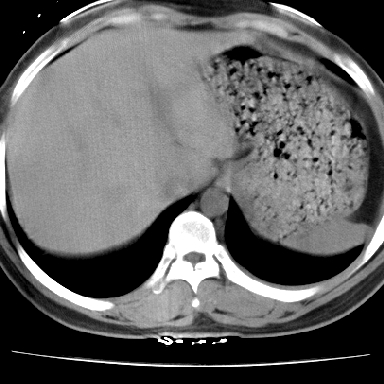

f 37 咳嗽1周,咯血1次,无浓痰,无明显发热

左下肺肿块影,内可以见小泡征,并见厚壁空洞形成,洞内缘凹凸不平,可见壁结节。靠近胸膜侧可见胸膜凹陷征。左侧胸腔内可见少量低密度积液影。右肺可见两处高致密的小结节影。

考虑:左下肺周围型肺癌伴右肺转移

左下肺肿块影,内可以见小泡征,并见厚壁空洞形成,洞内缘凹凸不平,可见壁结节。靠近胸膜侧可见胸膜凹陷征。左侧胸腔内可见少量低密度积液影。双肺可见多发性小结节影。

考虑:左下肺癌性空洞伴两肺转移

左下肺肿块影,内可以见小泡征,并见厚壁空洞形成,洞内缘可见壁结节。靠近胸膜侧可见胸膜肥厚粘连。双肺可见多发性小结节影。

考虑:左下空洞性肺癌伴两肺转移

偏心性厚壁空洞,壁结节,胸膜肥厚粘连,双肺多发性小结节灶。这么多典型征象,即使错了也错的有道理!

病灶与临床特点:1 位于下肺外围.2 与胸膜关系密切并明显胸膜反应.3 空洞内壁虽见壁结节,但还是较光滑.4 病灶周围明显渗出.5 另肺内多发小结节.6 临床症状轻,发病时间短.综合考虑:肺内特殊感染(霉菌感染).

左下肺有空洞,壁厚薄不均,壁结节,两肺多发小结节影,腋窝下可疑淋巴结肿大,综上所述考虑周围性肺癌并两肺转移可能性大,建议穿刺活检。

支持癌性空洞:壁厚,无液平,内壁不规则,外壁呈分叶状,较大,偏心性,壁结节,胸膜凹陷,转移灶。